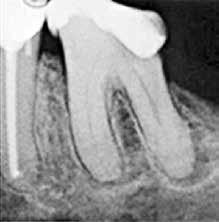

Fig. 2. Tidligere behandlet tand med insufficient eller helt manglende rodfyldning i kanalerne. A. Præmolarer i overkæben med tre insufficiente rodfyldninger og efterfølgende restaurering med stiftopbygning og krone. Desuden første molar uden synlig rodfyldning, men med restaurering, der inddrager pulpakammeret. B. Første molar i overkæben, som kun har synlig rodfyldning i den palatinale kanal. C. Insufficient rodfyldning eller overset rodkanal i første molar i overkæben.

Fig. 2. Previously treated tooth with no or inadequate root filling in canals. A. Maxillary premolars with 3 roots inadequately filled and restored with post and crown. Maxillary first molar with no visible root filling with restoration in pulp chamber and coronal restoration. B. Maxillary first molar with visible root filling only in the palatal canal. C. Inadequate root filling or missed root canal in maxillary first molar.

peroperative faktorer. En af dem er manglende behandling af en rodkanal, enten fordi den ikke blev fundet, eller fordi tandlægen ikke ledte efter den (Fig. 2A-C) (8,9). Det er påvist, at apikal parodontitis forekommer hyppigere i tænder med mindst én ubehandlet eller overset rodkanal (10). Accidentelle perforationer fører ofte til ekstraktion af tanden, men kan almindeligvis undgås med fornuftige endodontiske arbejdsgange (11). Ufuldstændig instrumentering eller forsegling af rodkanalen enten som følge af forkert rodmål eller på grund af fx instrumentfraktur, hyldedannelse eller overinstrumentering af den apikale konstriktion kan føre til, at infektionen persisterer. Rodfile kan frakturere som følge af cyklisk træthedsbrud eller vridningsbelastningsbrud, og incidensraten for brud ligger på 1 % (12). Det sted i tandsættet, der oftest giver anledning til instrumentfraktur, er den apikale del af en mesiofacial rodkanal i en molar (Fig. 3). Kraftig afbøjning af kanalen forøger risikoen for, at filen frakturerer (13). En for kort rodfyldning (> 2 mm fra radiologisk apex) har ligesom overfyldning med guttaperka en nedsat succesrate (14).